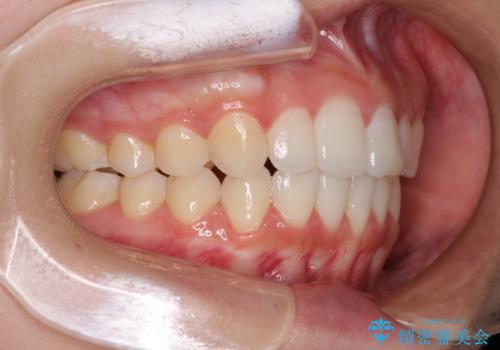

前歯のデコボコと突出感 インビザラインで改善

- 上下前歯のデコボコを気にして来院された患者様です。

インビザラインによる上下歯列の側方拡大と後方移動、IPR(歯と歯の間を削る)にるスペースの獲得により歯列を整えることとしました。

骨格的な左右差があったため、上下の正中を合わせることは困難かと思われましたが、何とか合わせることができました。

一方、骨格の差は改善できないため、奥歯の咬み合わせに物足りなさを感じました。

奥歯の咬み合わせによる不自由はなく、患者様に大変満足していただきました。